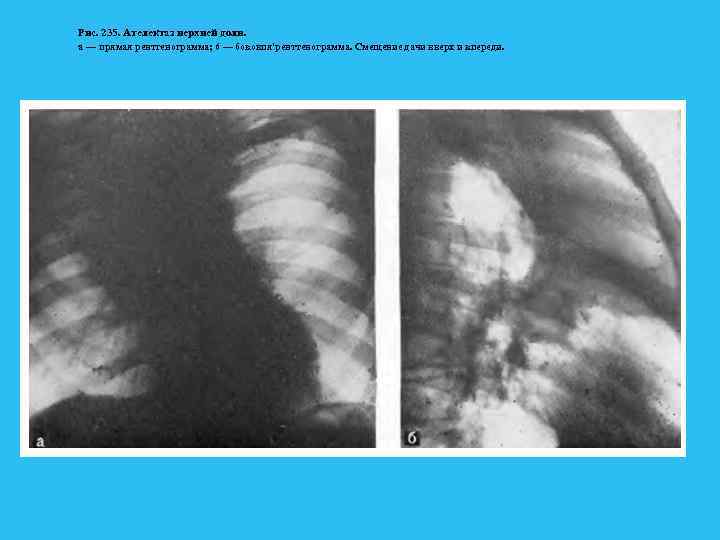

Немалое значение в правильной расшифровке рентгенограмм имеет знание закономерностей перемещения отдельных зон и сегментов при их спадении. Закономерности спадения долей представлены на рис. 234. Рис. 234. Схема спадений долой при ателектазах (по Anacker, 1063). а — верхняя доля; 6 — Средняя доли и язычок; в — нижняя доля.

Рис. 235. Ателектаз нерхней доли. а — прямая рентгенограмма; 6 — боковпя'ренттенограмма. Смещение дачи вверх и кпереди.

Ателектаз развивается при полной обтурации бронха опухолью, характеризуется полным рассасыванием воздуха из легочной ткани и резким ее объемным уменьшением. Кроме этих прямых признаков, как и при дистелектазе, большое диагностическое значение имеют вторичные симптомы, в той или иной степени сопутствующие ателектазу. Это, в первую очередь, смещение междолевой плевры и ее вогнутость в сторону объемного уменьшения. Выявляются также смещение корня легкого к ателектазу, средостения в сторону поражения, подъем купола диафрагмы и сужение межреберий на больной стороне, викарная эмфизема прилежащих участков легкого. Эти признаки также неспецифичны и указывают на объемное уменьшение легкого. В ателектазе также часто развиваются воспалительные и деструктивные изменения. Диагностировать их не всегда удается, лишь в отдельных случаях развиваются полости с газом и уровнями жидкости. Признаком тяжелой, обширной гнойной деструкции в ателектазе является нормальный размер доли или даже ее объемное увеличение такие случаи требуют неотложной хирургической помощи. При формировании ателектазов сегментов, долей соблюдаются определенные правила, знание которых облегчает топическую ориентировку и сокращает диагностический поиск. Во первых, любой ателектазированный участок смещается медиально и обязательно связан с корнем легкого. Во вторых, тень ателектаза смещается туда, где в норме располагались до этого сегмент или доля. В третьих, все доли и сегменты, граничащие с междолевой плеврой, в определенных проекциях обязательно сохраняют четкость очертаний. Участки же, не соприкасающиеся с плеврой, в любой проекции имеют размытый контур. Кроме медиального направления, доли спадаются следующим образом:

справа верхняя вверх и вперед, средняя вперед, нижняя вниз и кзади; слева верхняя вперед, нижняя вниз и кзади. Напомним сегменты, граничащие с междолевой плеврой: справа в верхней доле S 2 и S 3 , нижней S 6, S 7, S 8, слева в верхней S 1 2, S 4 и S 5, нижней S 6 и S 8. Оба сегмента средней доли ограничены междолевой плеврой. При формировании ателектазов междолевая плевра часто значительно изменяет свое положение и выявляется в проекциях, перпендикулярных тем, в которых она видна в норме. Например, при ателектазе средней доли горизонтальная междолевая плевра прослеживается только в боковой проекции, при ателектазе S 6 с обеих сторон (особенно часто слева) косая междолевая плевра отчетливо видна в прямой проекции. Сочетание ателектазированных долей и сегментов указывает на пораженный бронх, но не всегда эта зависимость соблюдается в полной мере. При резком стенозировании просвета бронха может не быть признаков нарушения вентиляции ткани легкого. И наоборот, при четко видимом просвете может сформироваться дистелектаз паренхимы. Такой вариант особенно характерен для рака Б 1 2 слева, часто имеющего перибронхиальный стелющийся рост и сопровождаемого симптомом "удлинения бронха".